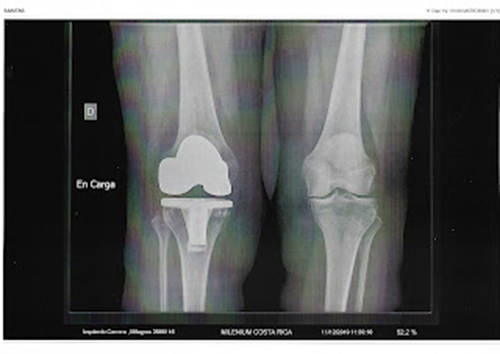

El diagnóstico del

síndrome piramidal lo realiza el traumatólogo, osteópata, especialista en

unidad del dolor, unidad de columna, medicina del deporte, etc., mediante una

exploración manual profunda de la zona de las nalgas, atravesando el músculo

glúteo mayor y, si es necesario, a través de la pelvis mediante exploración

rectal o vaginal. Para completar el estudio, aunque no siempre es necesario,

puede realizarse una radiografía en carga para descartar una posible dismetría

de las extremidades inferiores o asimetría lumbar. En ocasiones, una

gammagrafía puede ayudar a localizar el área de activación del dolor.